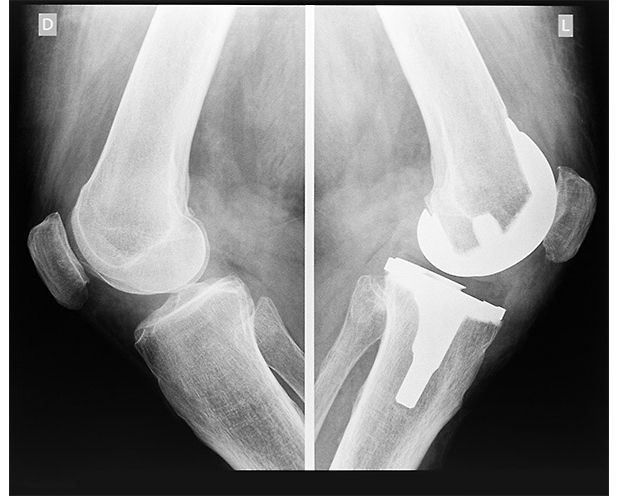

Design Better Implants: Is Bone Material Stronger than Steel? Bone typically has an elastic modulus that is like concrete but it's 10 times stronger in compression. As for the stainless-steel comparison, bone has a similar compressive strength but is three times lighter. So, what happens when a bone becomes so compromised that human engineers need to step in?